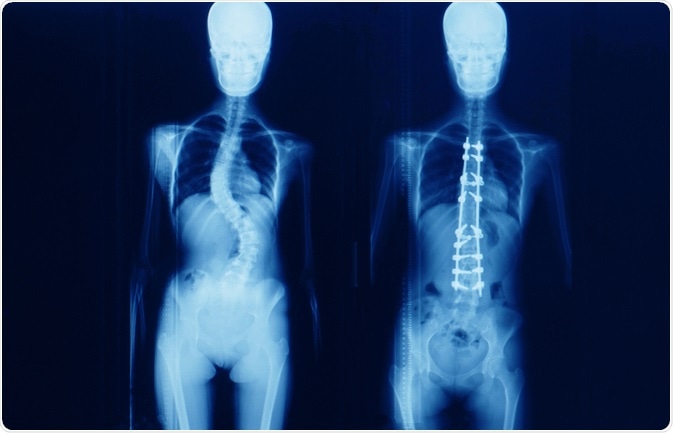

scoliosisImage Credit: Yok_onepiece / Shutterstock.com

Spinal fusion is the most common surgery for patients with scoliosis that have finished growing and involves a graft of bone onto the spinal vertebrae that eventually heal together to form a solid, rigid mass of bone. Although this process may restrict the movement of the spine, it prevents the curvature from becoming worse and may correct severe cases.

There are two main techniques that may be used: anterior fusion provides access to the spine via an incision on the side of the chest wall, and posterior fusion utilizes an incision on the back and metal instruments for the curve correction. The bone graft can be attached to the spine with a combination of metal rods, screws, hooks and wires, which are left in place permanently.